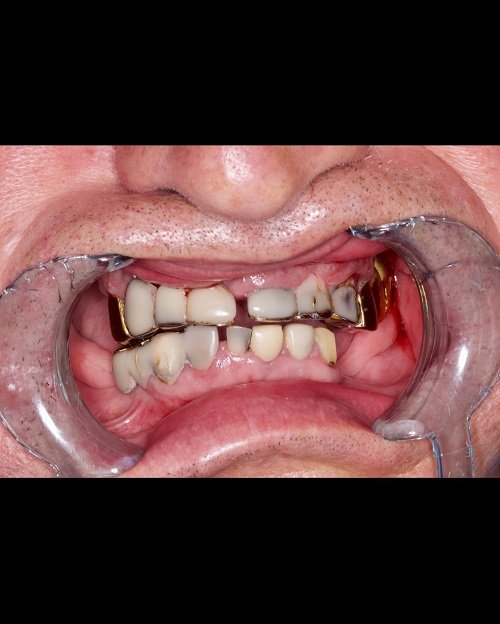

«Все на 4-х имплантатах»

«Все на 4-х имплантатах» - данную методику мы применяем нашим пациентам с полным отсутствием зубов.

Именно эта методика позволяет позволяет в кратчайшие сроки, около 3-5 дней зажить полноценной жизнью.